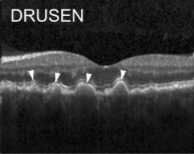

Eye diseases or ocular dysfunctions are fairly frequent in the general population, particularly among the elderly. The most significant anomalies in the eyes are choroidal neovascularization (CNV), diabetic macular edema (DME), and drusen accumulation in the macular region. In the recent decade, optical coherence tomography (OCT) has become one of the most rapidly evolving medical imaging technologies which can capture blood flow, polarization state, structural data, elastic properties, and molecular content, among other things, in biological tissues [1]. Optical diffraction and absorbance of biological tissues can be accurately measured with OCT and thus some diagnostic measures benefit from it.

Optical coherence tomography (OCT) images were selected from retrospective cohorts of adult patients from different hospitals around the world. OCT Images are labeled as (disease)-(randomized patient ID)-(image number by this patient) [11] and Fig 1 shows some examples of OCT images. Image properties are presented in Table II and the distribution of image quantity is presented in Table III. Custom image generators resize images to 224x224x3 and normalize them